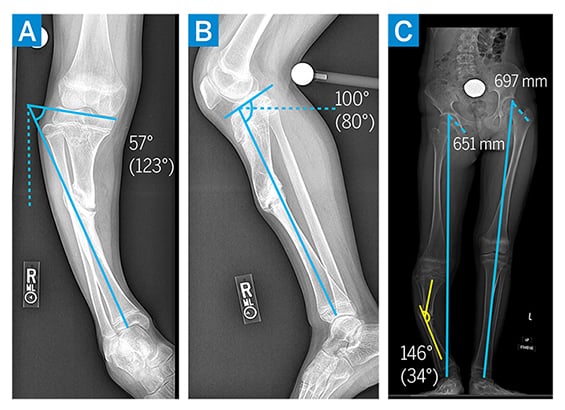

The patient underwent right proximal tibial epiphysiodesis, fibular osteotomy, and distraction osteoplasty with a hexapod frame. The nonunion was found to be nonosseous and hypertrophic in nature, allowing for correction through the nonunion site without need for additional osteotomy. The intramedullary canal proximal and distal to the nonunion site was drilled, and intraoperative cultures were obtained to confirm absence of ongoing infection. A hexapod ringed external fixator was applied to allow for simultaneous correction of the varus deformity and gradual lengthening (Fig. 2A). By 2 months postoperatively, the patient’s varus deformity was significantly improved and limb length discrepancy had improved to 3 cm (Fig. 2B–C). Her external fixator was removed 3 months postoperatively, with a residual recurvatum deformity noted (Fig. 3A–B). Shortly thereafter, she underwent right proximal tibial metaphyseal osteotomy and gradual deformity correction with a hexapod ringed external fixator (Fig. 3C). By 3 months postoperatively, coronal and sagittal alignment were normalized and the external fixator was removed (Fig. 3D).

Figure 2

Figure 2: (a–b) Perioperative imaging demonstrating tibial intramedullary canal drilling and frame placement. (c) At 3 months postoperatively, imaging demonstrated improved alignment and leg length discrepancy.